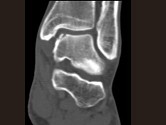

- 单项选择题男,17岁, 踝关节疼痛,关节作响, 结合图像,最可能的诊断是 ( )

B、剥脱性骨软骨炎